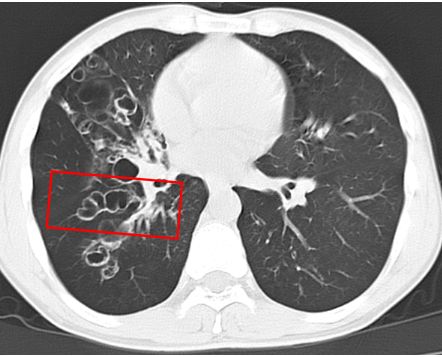

管径一致,形成典型的双轨征(长箭头)

低氧血症的42岁男性:左侧舌下段肺动脉双轨征(短箭头) [8]值得一提的